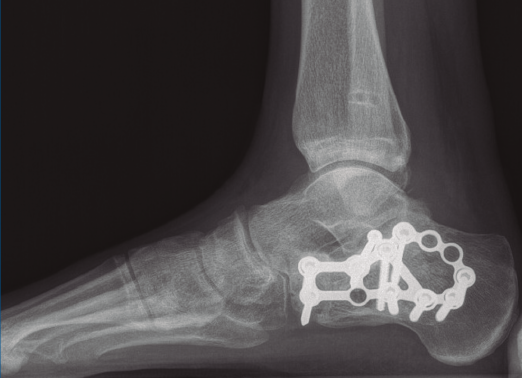

Bajo isquemia se realiza un abordaje lateral en L ampliado y se expone el calcáneo. Se trató de realizar una reducción abierta empleando un clavo de Steinmann (maniobra de Westhues), lo cual no se consiguió hasta la realización de un alargamiento percutáneo del Aquiles. Se comprobó bajo escopia la correcta reducción tanto de la fractura del calcáneo como de la luxación al nivel del tobillo. Se realizó una fijación con una placa de calcáneo, con 7 tornillos de esponjosa de 4 mm de diámetro (2 de ellos bloqueados) tras la reducción de la carilla posterior con un tornillo a compresión de 3,5 mm.

Figura 9. Control radiográfico posquirúrgico, anteroposterior.

Figura 10. Control radiográfico posquirúrgico, lateral.

Se dio de alta el día siguiente a la cirugía con un buen control analgésico. En la radiografía de control postoperatoria presentó una correcta reducción tanto de la fractura de calcáneo como de la articulación tibioperoneo astragalina (Figuras 9 y 10). Se citó en consultas externas 2 semanas después para la retirada de la sutura, presentado un buen aspecto las heridas quirúrgicas (Figura 11), y para la colocación de un botín de yeso. Dicho botín fue retirado al mes y medio de la cirugía, colocándose una ortesis estabilizadora de tipo Walker y autorizándose la carga parcial y progresiva, comenzando la rehabilitación.

A los 9 meses únicamente presentó dolor ocasional al nivel de la articulación subastragalina y molestias en la planta del pie al deambular descalzo, por lo que se pauta plantilla amortiguadora, con la que mejora notablemente la sintomatología. Presentó una puntuación de 83 sobre 100 en la escala de la American Orthopaedic Foot and Ankle Society (AOFAS), ligeramente superior a la media descrita en estudios previos(2,3). Radiográficamente se evidenció una anatomía restablecida del calcáneo y de la sindesmosis, así como una altura adecuada de ambos tobillos (Figuras 12 y 13). Dada la buena evolución, se decidió continuar con el seguimiento anual del paciente sin realizar la extracción del material de osteosíntesis, para valorar la necesidad de una futura artrodesis sub­astragalina.